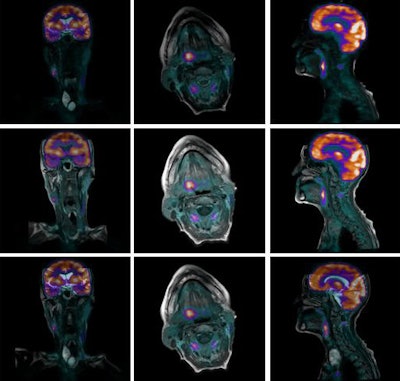

While rigid registration-based fusion has been used for many years, it is restricted to applications such as brain imaging, for which a translation and rotation are typically sufficient to correct for the misalignment. In contrast, DIR is capable of correcting nonrigid motion, hence in principle it can be applied in all areas of the body. Figure 1 illustrates the importance of using deformable over rigid registration, even in a head and neck case. The resulting software PET-MRI is shown in figure 2.

Figure 2: Software PET-MRI fusion for a head and neck case. The CT-MRI deformable image registration is used to align the PET with all of the MRI sequences. Here, all the MR images are rendered in their original orientation fused with the FDG-PET.

Importantly, DIR can correct for differences in patient positioning, and so the PET/CT and MRI scans can be taken days or even weeks apart using standard protocols. Moreover, for certain diseases the acquisition of both modalities is the standard of care in many institutions, and no additional scans need to be performed. The example shown in figure 2 was generated with images acquired a week apart as part of the patient's management.